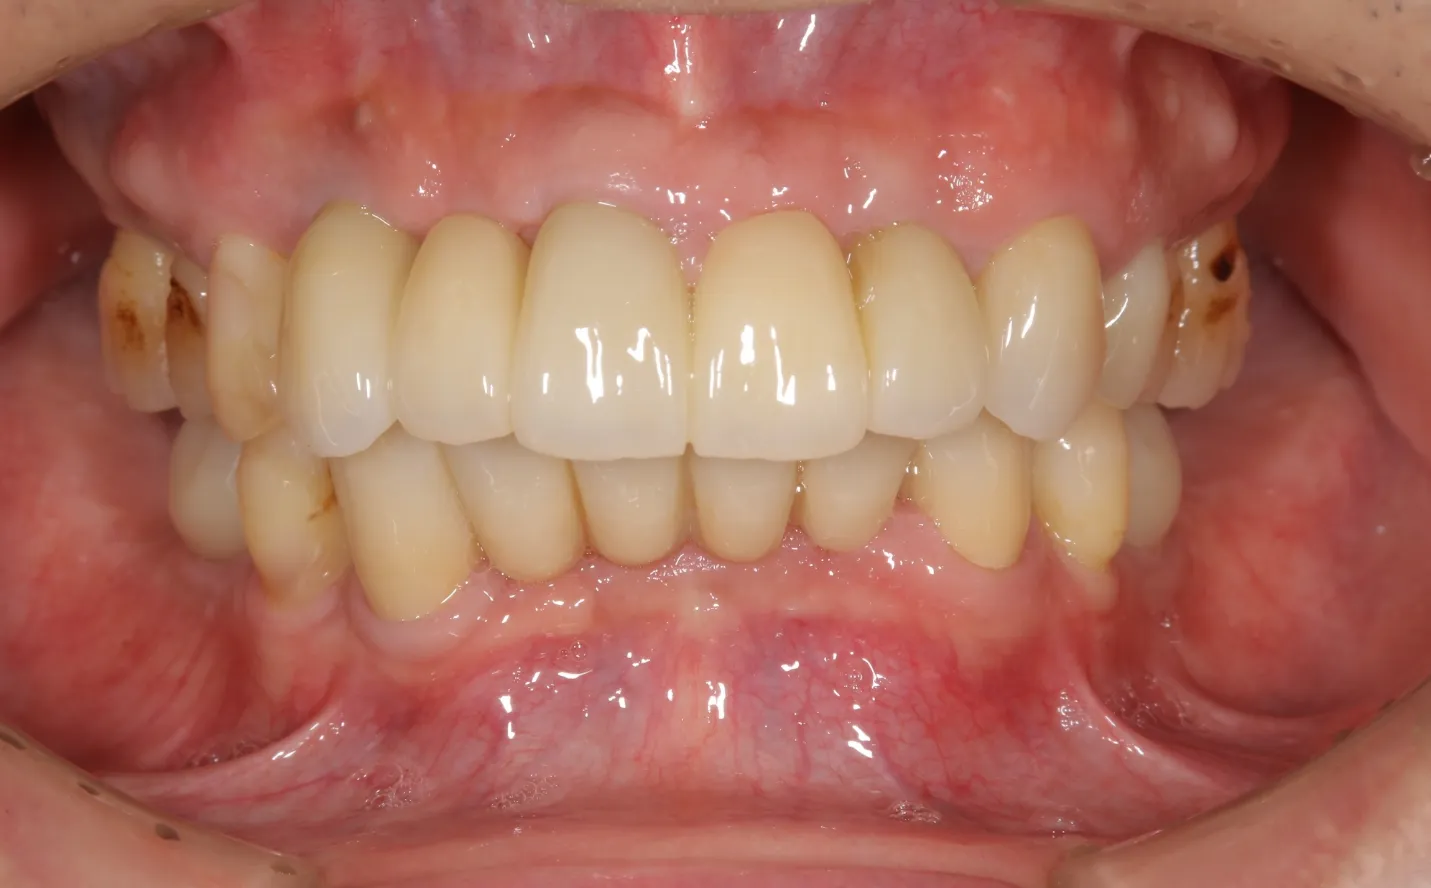

インプラント治療症例

【症例1】

主訴

噛めない。不自由なく食事をしたい。

年齢・性別

50代男性

治療内容

上下顎フルインプラント

期間

1年2ヶ月

費用

7,279,000円